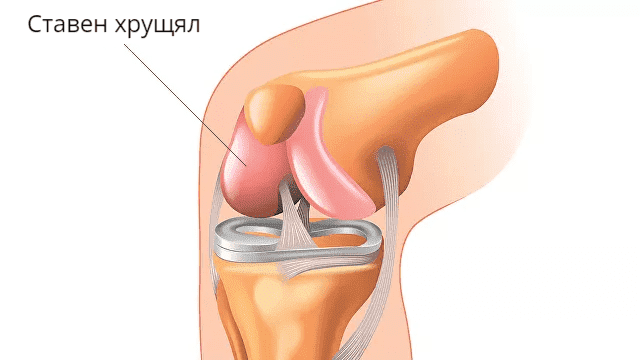

Най-честите ставни заболявания са:

- остеоартрит (хронично дегенеративно-дистрофично заболяване, което води до деформации на ставите);

- артрит (възпалителни заболявания на ставите от различно естество);

- бурсит (възпаление на синовиалната торбичка);

- дисплазия на тазобедрената става (вродено нарушение на развитието);

- подагра (увреждане на ставите от метаболитен характер).

Обикновено всички тези заболевания са трудни за лечение.